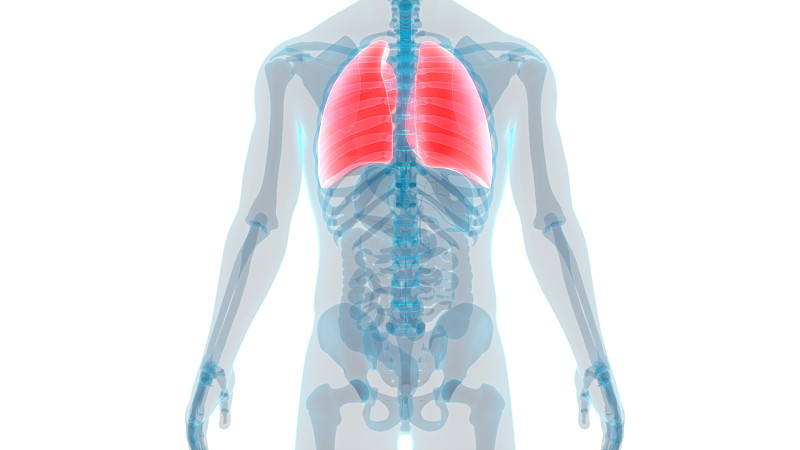

人体呼吸系统肺解剖详情

人体呼吸系统肺解剖学详情

人体呼吸系统肺解剖学详情

人体呼吸系统肺解剖详情

人体呼吸系统肺解剖详情

人体呼吸系统肺解剖详情

人体呼吸系统肺解剖学详情

人体呼吸系统肺解剖详情

人体呼吸系统肺解剖详情

人体呼吸系统肺解剖详情

人体呼吸系统肺解剖详情